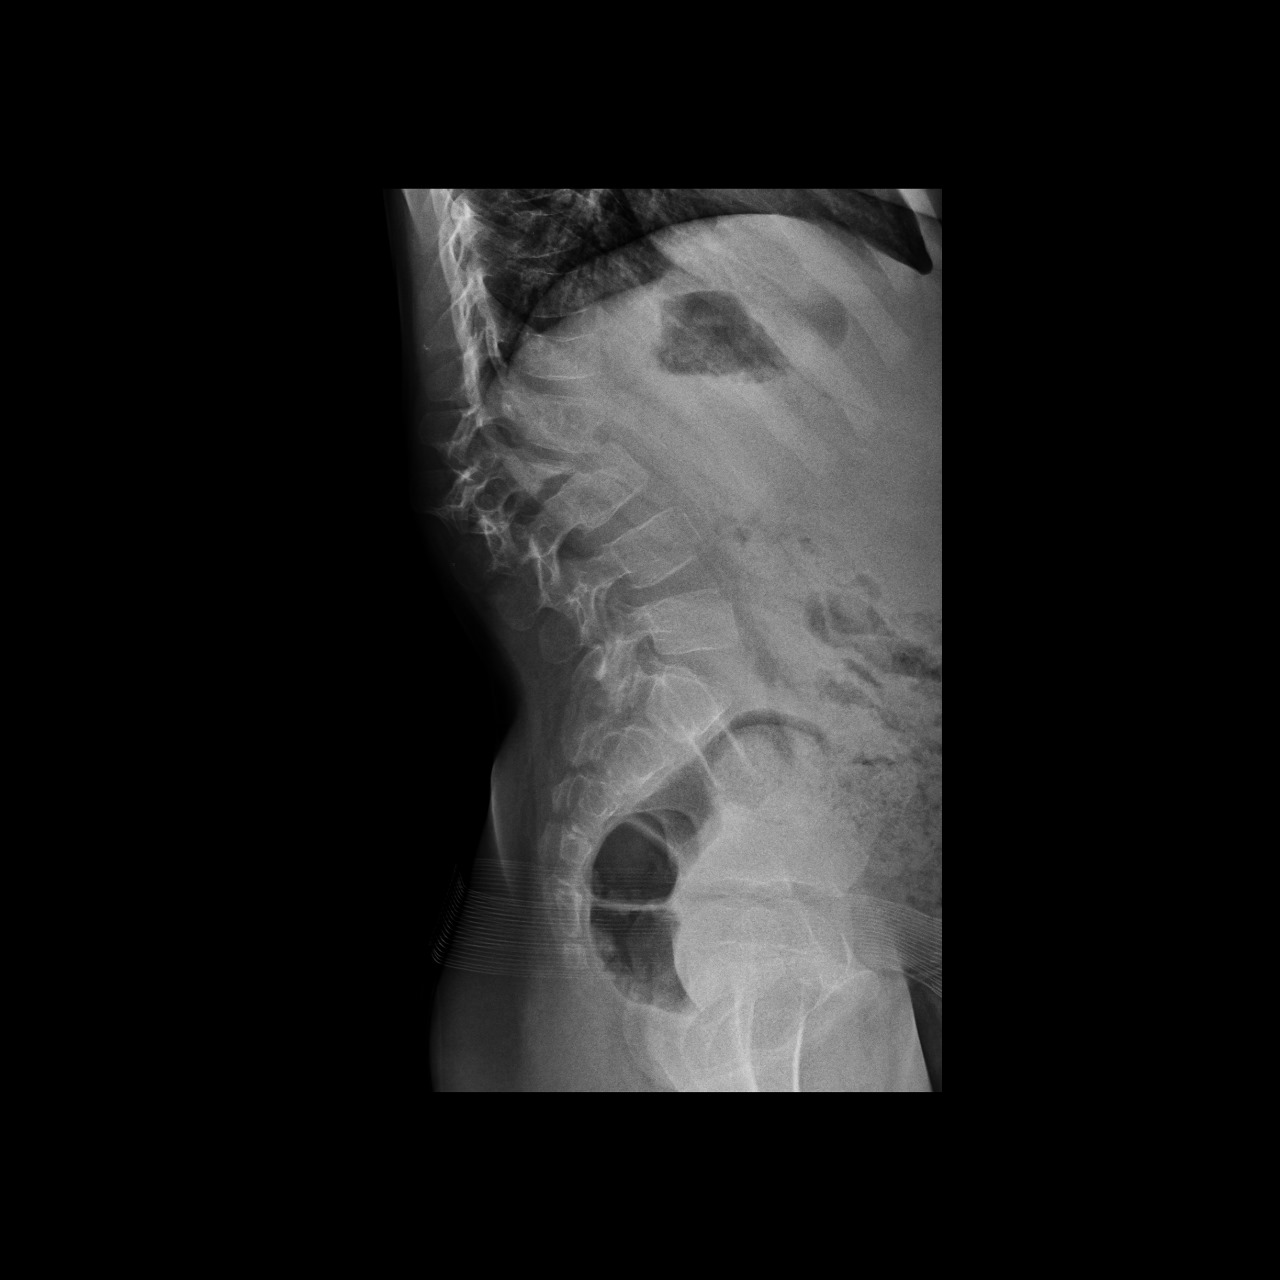

7 años

Tumoración lumbar